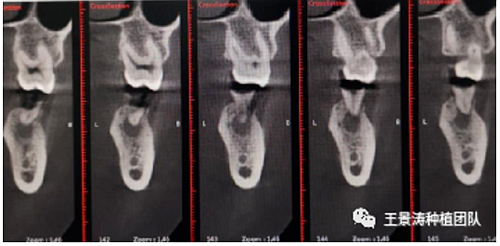

左側(cè)下頜第二磨牙及右側(cè)下頜第一磨牙同時即刻種植病例。患者年輕女性,無系統(tǒng)性疾病。37及46殘冠及殘根,且46劈裂,無法冠修復(fù),必須拔除。37根尖慢性炎癥,大量肉芽組織存在,46根分叉較高,根分叉骨質(zhì)尚可。CBCT示:根尖骨質(zhì)至下牙槽神經(jīng)管距離可滿足種植體的初期穩(wěn)定性,遂考慮即刻種植,并在種植體周邊填入骨粉并覆蓋骨膜,雙側(cè)的種植體初期穩(wěn)定性相差無幾,但考慮到37根尖慢性炎癥較大,遂給予埋入式種植。